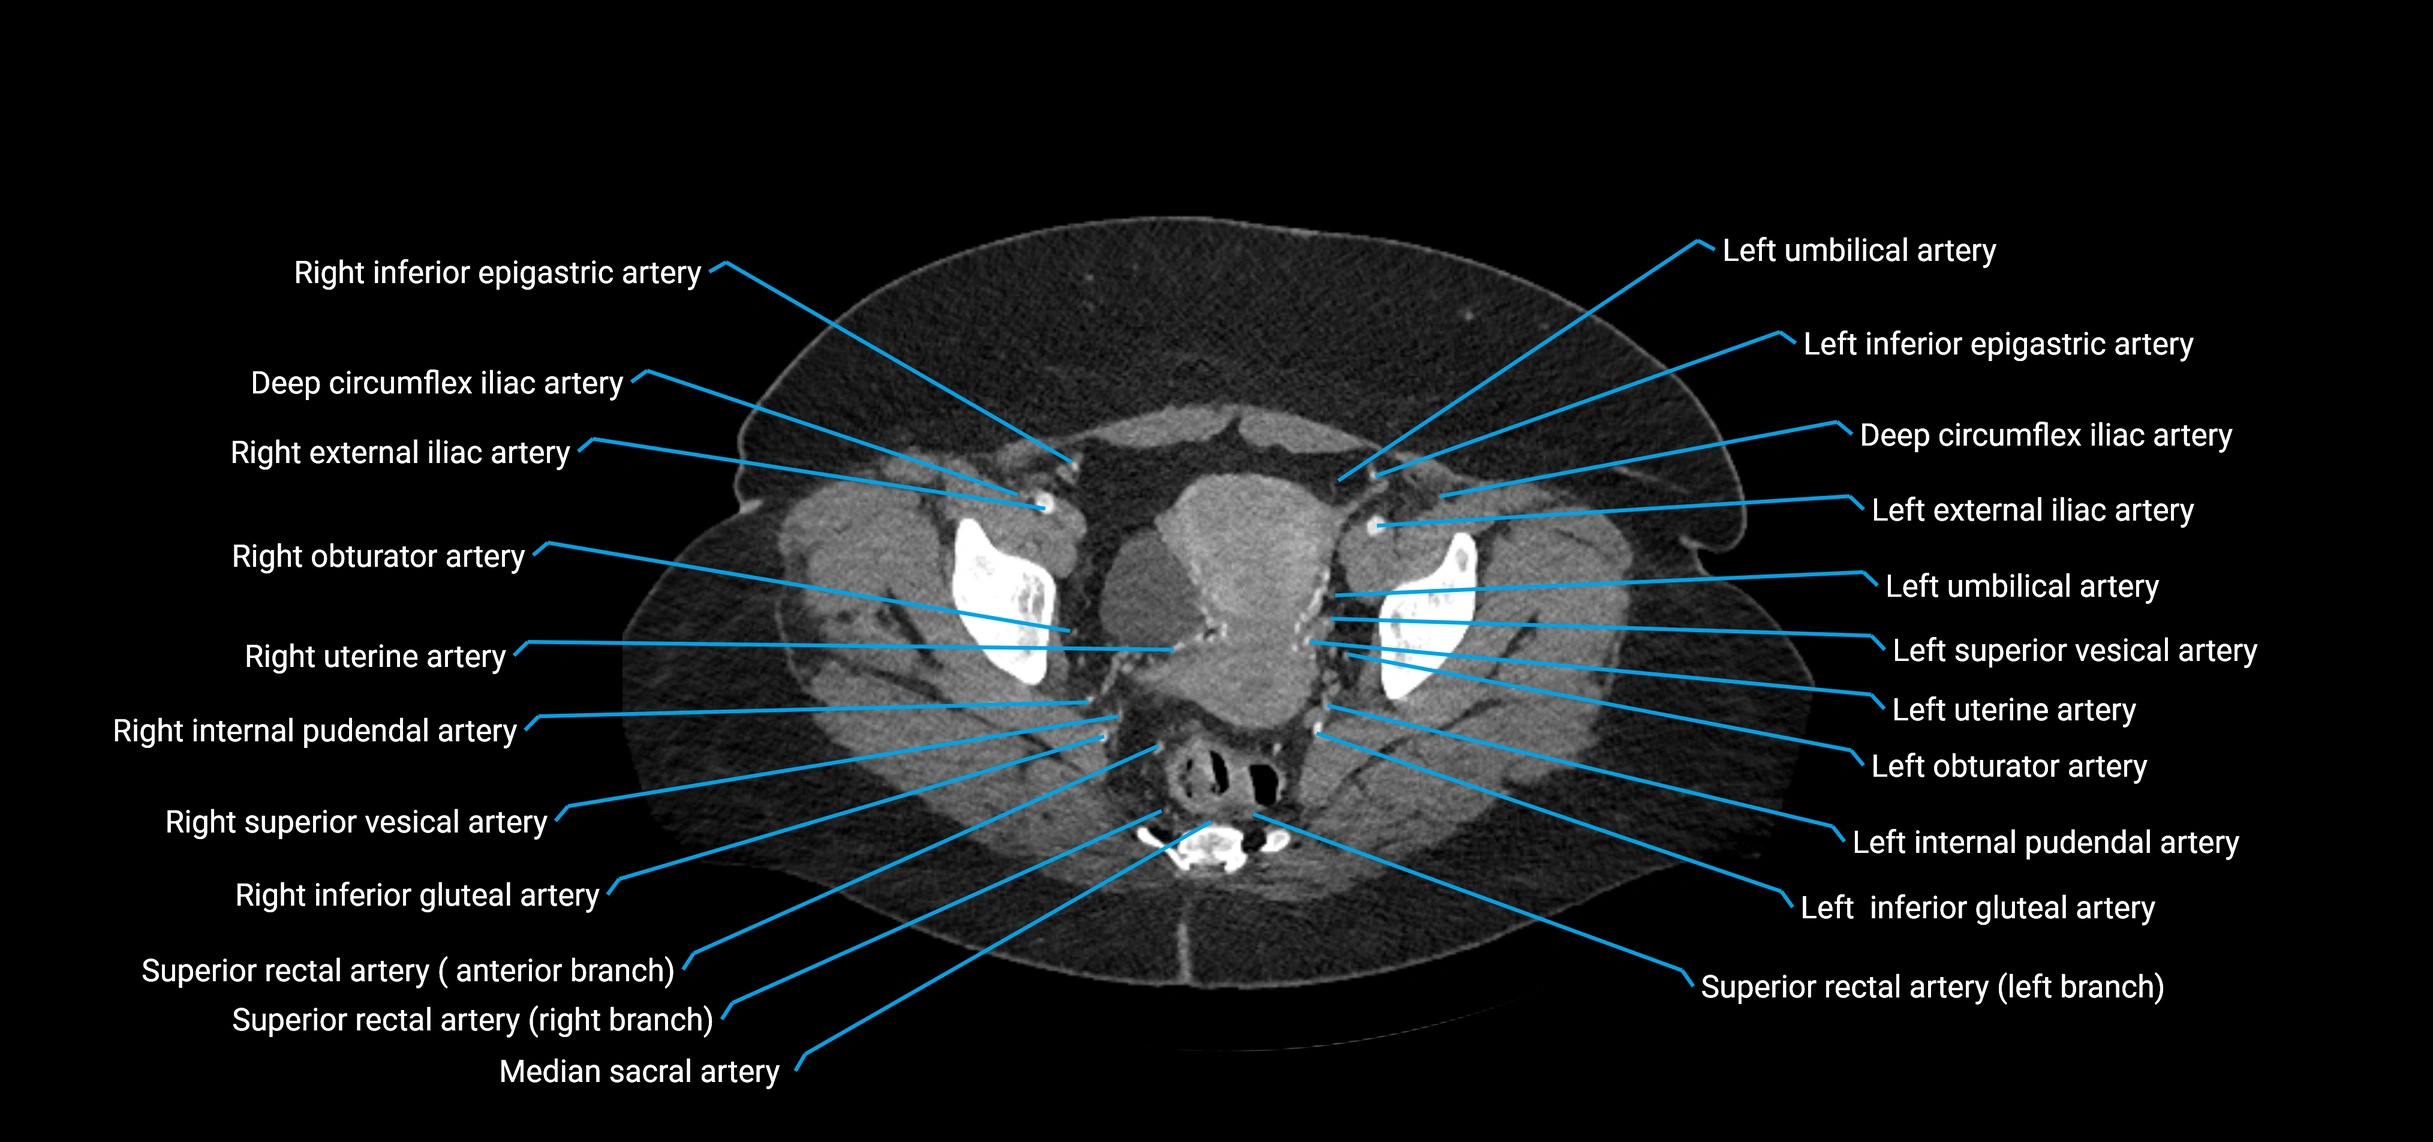

Contrast-enhanced CT (CTA):

• Gold standard for abdominal aortic imaging

• Provides excellent detail of lumen, wall, aneurysm, thrombus, and branch vessels

• Multiplanar and 3D reconstructions help in aneurysm measurement, stent graft planning, and dissection evaluation

• Detects acute rupture, traumatic injury, or occlusion with high sensitivity